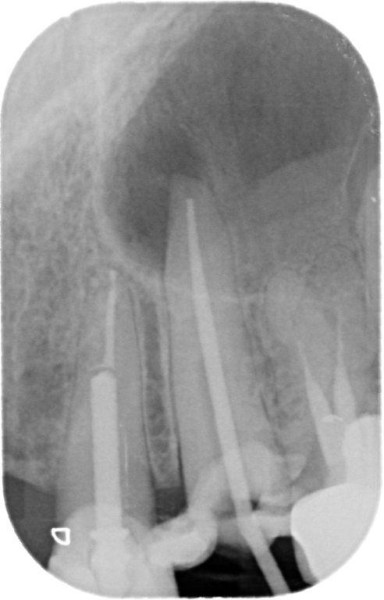

Post removal cases